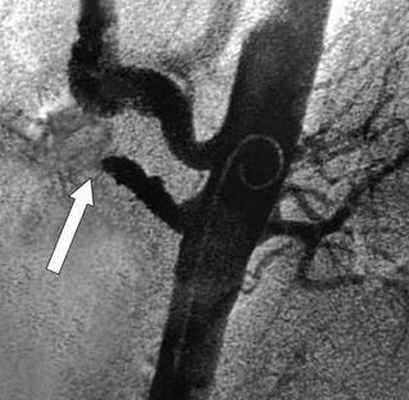

Рентгеновская ангиография

Метода введения контрастного вещества непосредственно в интересующие артерии. Проводится через доступ к артериям на руке или на ноге. Позволяет прицельно изучить проходимость брыжеечных артерий и одновременно выполнить вмешательство по восстановлению проходимости закупоренной артерии. Ренгтеноангиография выступает диагностическим и лечебным методом одновременно. С помощью специальных катетеров и инструментов возможно проведение рассасывания тромбов (тромболизиса) или его удаления - тромбэктомии.